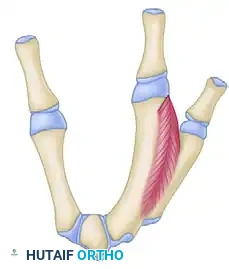

The index finger is transposed following the osteotomy of the index metacarpal base and the release of the first dorsal interosseous muscle.

- Bone Fixation: If the third metacarpal base is hypoplastic or small, shape the proximal end of the transposed index metacarpal into a peg and impale it directly into the medullary canal of the third metacarpal base.

- If adequate bone stock is present, reduce the osteotomy and fix the index metacarpal to the third metacarpal base using crossed or parallel Kirschner wires (K-wires).

Additional subperiosteal release of the first dorsal interosseous allows tension-free transposition. The inset demonstrates the necessary rotation (up to 45 degrees) required to prevent digital overlap during flexion.

Clinical Pearl: Rotational alignment is the most critical aspect of the osteotomy. The transposed digit must be supinated (often up to 45 degrees) to ensure it flexes symmetrically into the palm without scissoring over the ring finger.